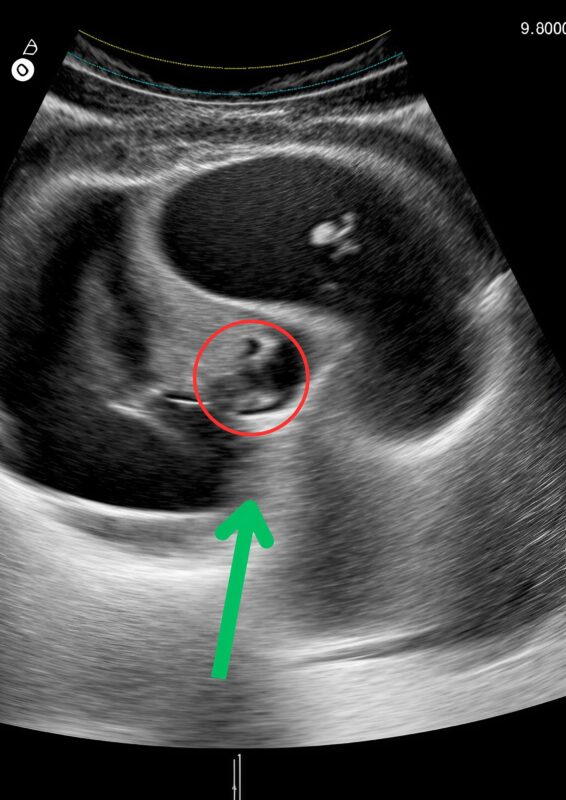

Ինձ տարան զննման սենյակ, որտեղ բժիշկը նշանակեց ուլտրաձայնային հետազոտություն։ Ես պառկեցի բազմոցին՝ նյարդային և ամաչկոտ, լուռ հույս ունենալով պարզ արդյունքի՝ գուցե մի փոքր վերք, թեթև բորբոքում, կառավարելի ինչ-որ բան ։ Տեխնիկը տեղափոխեց ուլտրաձայնային սարքը ստամոքսիս վրայով, և էկրանին թարթում էին ձևեր և ստվերներ։ Ապա բժիշկը մոտեցավ՝ աչքերը լայն բացած, դեմքը՝ անշարժ։

«Սա… սա չի կարող պատահել», — ասաց նա։ «Դա անհնար է»։ Ստամոքսս սեղմվեց։ Ես նայում էի մոնիտորի վրա՝ չկարողանալով հասկանալ, թե ինչ էի տեսնում ։ Էկրանի վրա ձևերը բոլորովին այլ էին, քան ես սպասում էի։ Խուճապի ալիք տիրեց ինձ։

Եվ հետո ես հասկացա՝ հղի եմ ։ Արտաքին ախտանիշներ չկան, կլոր փորիկ չկա, վաղ նշաններ չկան, և այնուամենայնիվ, էկրանին կյանք էր աճում իմ ներսում։ Սիրտս բաբախում էր թեթևության և ցնցման միջև։ Արրաբիատա մակարոնեղենից հետո կրած այրող ցավերը այլևս պարզապես ստամոքսի գրգռվածություն չէին. իմ մարմինը արձագանքում էր հղիությանը։ Կծու սնունդը գրգռել էր զգայուն ստամոքսս, բայց իմ անհարմարության իրական պատճառը ամբողջ ընթացքում աչքերիս առաջ էր ։